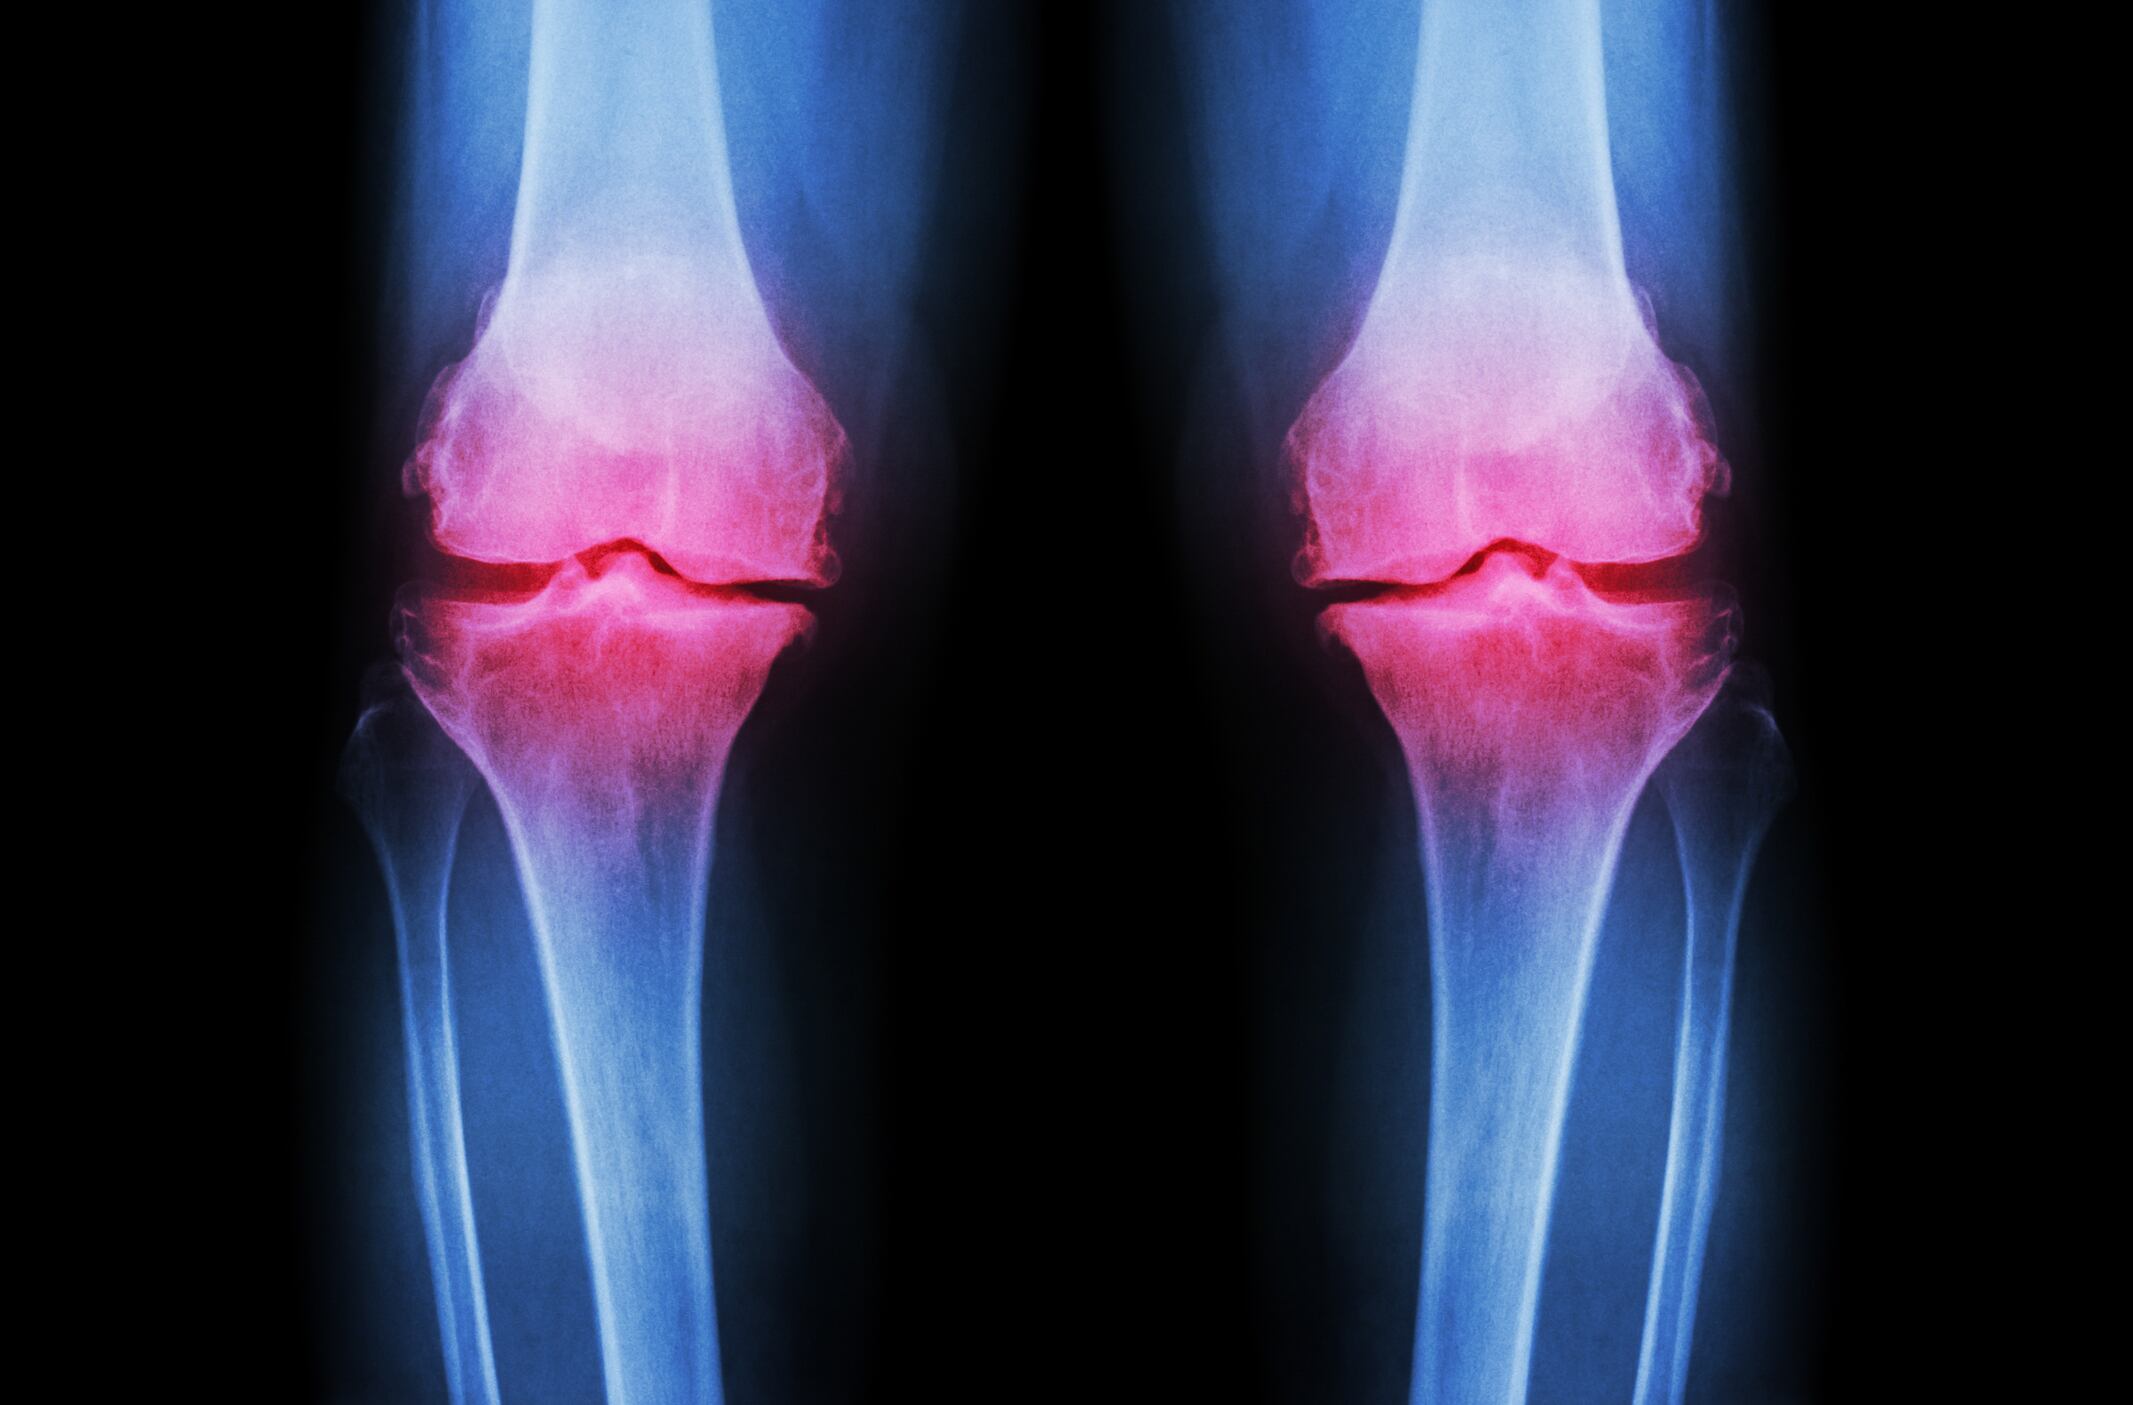

Performed in people suffering from knee osteoarthritis (OA), the new study indicated that a 450 mg per day dose of the eggshell membrane was associated with improved walking distance and ability and reduced stiffness, according to findings published in the Journal of Medicinal Food.

Scientists led by Dr Susan Hewlings from Central Michigan University also reported that the greatest benefits associated with the eggshell membrane supplement were for people with more severe OA.

Dr Hewlings and her co-workers recruited 88 adults with knee osteoarthritis and randomly assigned half of them to consume the eggshell membrane supplement (450 mg per day) or placebo for 12 weeks.

Results showed that, compared to baseline, participants in the BiovaFlex group displayed improvements in scores on the Western Ontario McMaster Osteoarthritis Index (WOMAC) and in the six-minute walk test (6MWT) after just five days.

Significant improvement over the placebo group was observed at week 12, wrote the researchers.